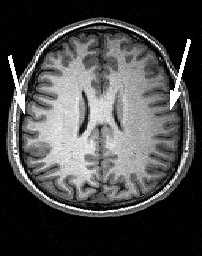

Центральная борозда (sulc.centralis) лучше видна в сагиттальной плоскости. Она расположена по середине между параллельными ей прецентральной и постцентральной бороздами. Существует много вариантов строения и хода борозды. Обычно она имеет значительную протяжённость и идёт в передне-нижнем направлении от межполушарной щели к Сильвиевой щели, которой достигает не всегда. Нижний конец борозды, либо продолжается в основном её направлении, либо загибается назад. Центральная борозда может прерывается по ходу. В поперечной плоскости на верхних срезах борозда имеет наибольшую протяжённость, доходя почти до межполушарной щели. Чем ниже срез, тем короче на нём центральная борозда. На уровне боковых желудочков она едва прослеживается . Центральная борозда разграничивает лобную и теменную доли .

МРТ головного мозга. Аксиальный срез на уровне крыши боковых желудочков. Центральная борозда (стрелки).